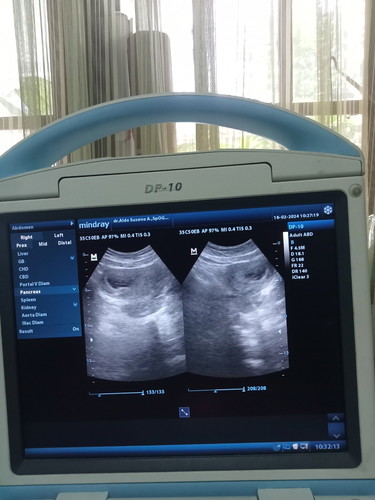

Hamil 9 minggu

Hamil 9 minggu baru ada kantung aja normal gk bun?